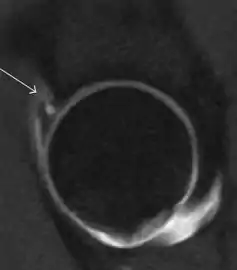

Synovial chondromatosis can be confidently diagnosed by X-ray when calcified cartilaginous chondromas are seen. However, other synovial proliferative processes, such as pigmented villonodular synovitis, require MRI for accurate diagnosis, although noncalcified synovitis can be suspected in radiographs by indirect signs, such as soft tissue swelling and/or erosions in the femoral head, femoral neck, or acetabulum (Figure 7).[1]

Figure 7:

Axial CT image of pigmented villonodular synovitis eroding the posterior cortex of the femoral neck.[1]

Sagittal T2* gradient echo image showing a posterior soft tissue mass with hypointense areas secondary to hemosiderin deposition.[1]

X-ray of synovial chondromatosis.[1]

CT of synovial chondromatosis.[1]